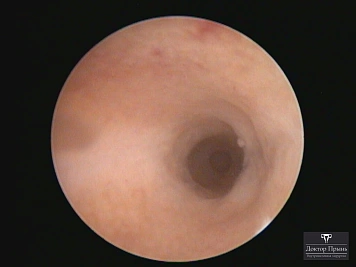

Фотогалерея

Синехии, рассечённые Прынь Д.В.